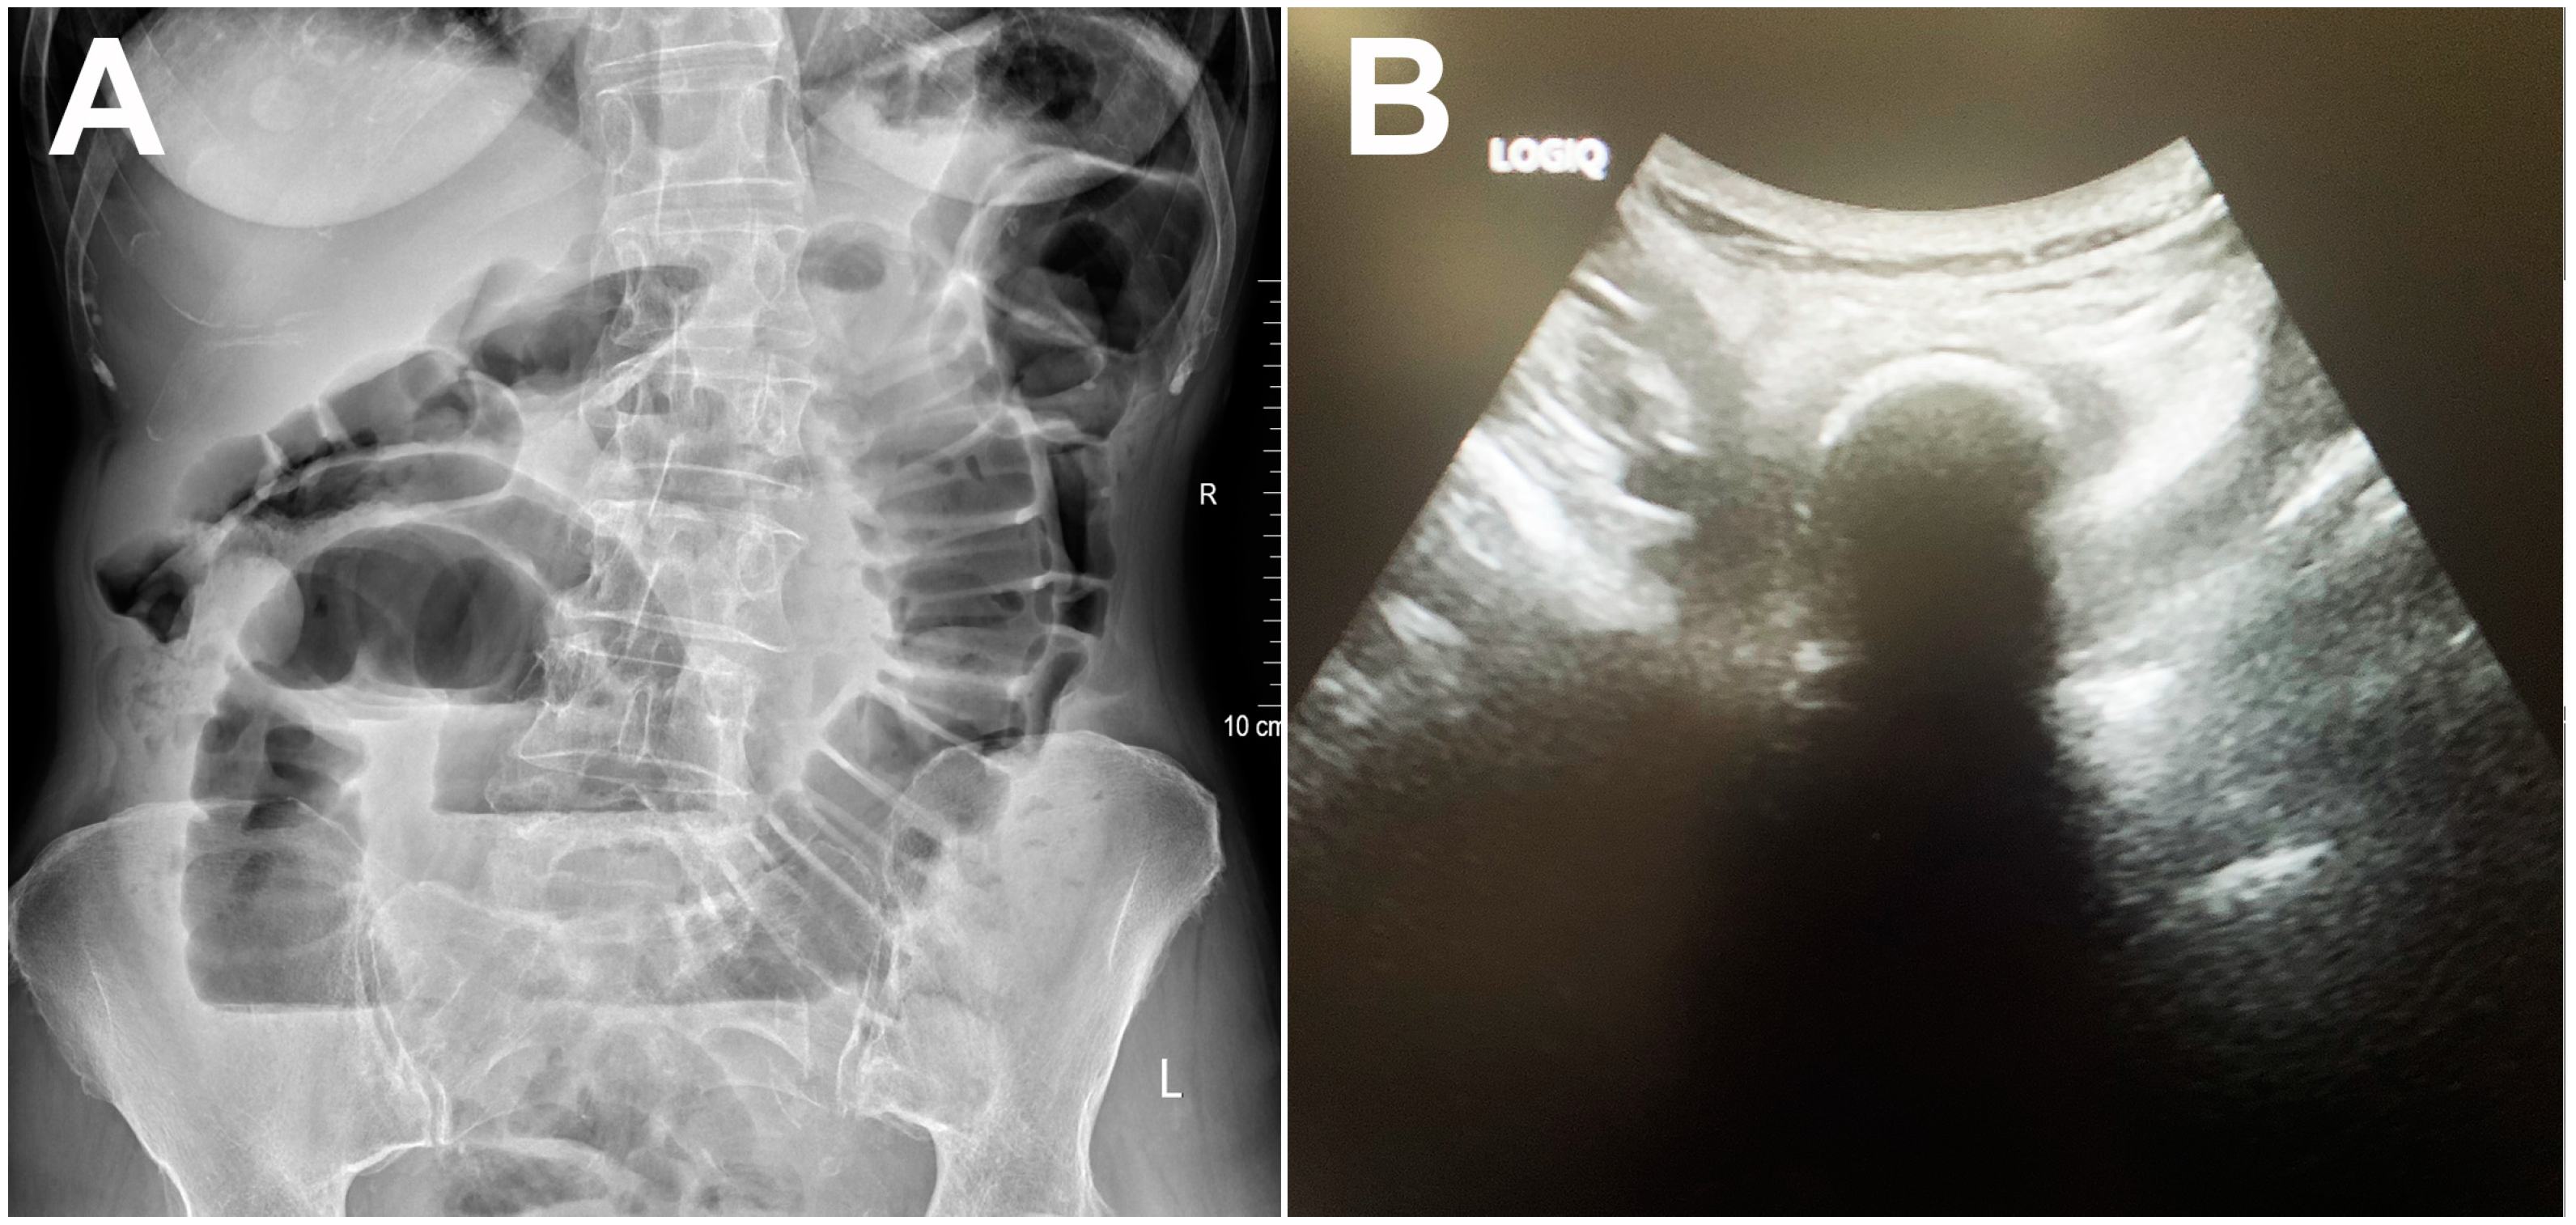

| Calcified bezoar (“Bezoar egg”) | Hyperechoic oval structure with posterior acoustic shadow within the bowel lumen | Oval, clearly demarcated mass with centrally placed gas | T1w and T2w hipointense oval mass with layered structure |

| Non-calcified bezoar (trichobezoar, phytobezoar, lactobezoar) | Arc-like surfaced intraluminal mass with posterior acoustic shadow | Oval or tubular masses with clear boundaries located inside the intestinal lumen, with mottled gas density | Oval mass with low T2w signal and a low to intermediate T1w signal intensity |

| Gallstone ileus | Hyperechoic oval structure with posterior acoustic shadow | Oval calcified or isodense intraluminal mass, presence of pneumobilia and cholecysto-enteric fistula | Oval mass with a homogenously low signal intensity on T1w and T2w |